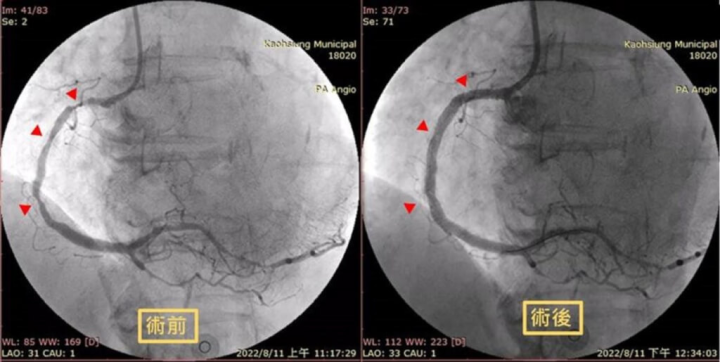

63歲大學教授近日忽然感覺胸口悶痛,且疼痛感輻射到脖子和下巴,到高雄市立聯合醫院急診才發現是嚴重急性心肌梗塞,及時手術救回一命。(高雄市立聯合醫院提供)

高市聯醫心臟介入團隊隨即啟動緊急心導管並放置金屬塗藥支架,打通阻塞的右冠狀動脈,並經過加護病房住院調養後,使情況穩定,如今已準備出院。